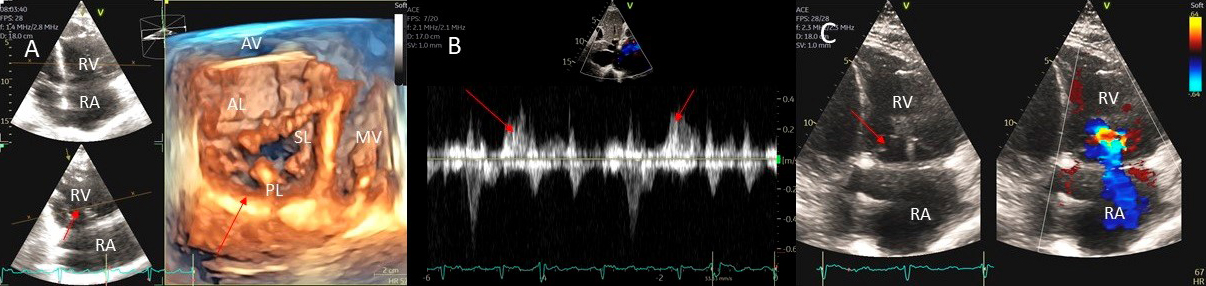

Examples of valvular injury directly from implantable cardioverter-defibrillator lead placement (Fig. 5A–C) or a permanent pacemaker (Fig. 6A–C) or endomyocardial biopsy in cardiac transplant recipients (Fig. 7A,B) are shown.

Fig. 5.Tricuspid regurgitation induced by pacemaker lead impingement. (A) 3D transthoracic echo showing and dilated RV, RA and anterior leaflet impingement by the device lead (red arrows). (B) Inspiratory systolic hepatic flow reversal (red arrows), which suggests severe TR. (C) Apical four chamber view showed severe tricuspid regurgitation. RA, right atrium; RV, right ventricle; AV, aortic valve; AL, anterior leaflet; PL, posterior leaflet; SL, septal leaflet; MV, mitral valve.